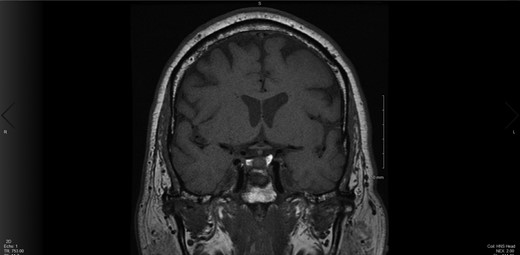

The decision was made by a multidisciplinary team including neurosurgery and otolaryngology to proceed with endoscopic endonasal transsphenoidal resection of the pituitary tumor with a possible fat graft harvest. This surgery was exploratory in nature to resect this microadenoma and 70–80% of the left side of the gland was removed (Fig. 4). The resected tissue was sent for pathology, which showed partially crushed pituitary parenchyma without atypia. Pathology also showed a focal loss of reticulin architectural pattern, suggestive of an adenoma. There were no complications noted during time of surgery. He did not require chronic steroids post-operatively. He received one dose of desmopressin postoperatively due to an episode of diabetes insipidus.